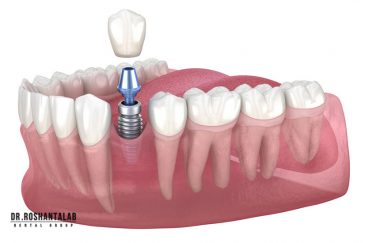

تجربه کاشت دندان دیجیتال و بدون درد در ۳ دقیقه! استفاده از برترین برندها زیر نظر جراح، با هزینه مناسب و خدمات کامل از کاشت دندان تا روکشارتودنسی دندان

انتخاب بهترین متخصص ایمپلنت که به تکنیکهای روز دنیا مسلط باشد، تضمینکننده سلامت فک و زیبایی لبخند شماست. در کلینیک دندانپزشکی دکتر روشنطلب، ما با بهرهگیری از تجهیزات دیجیتال در ۵ شعبه فعال (تهران، اصفهان، رشت و استانبول ترکیه)، خدمات تخصصی کاشت ایمپلنت دندان را برای بیمارانی که کیفیت و دقت برایشان اولویت دارد، ارائه میدهیم. در این متد، پروسه درمان با ظرافت بالا انجام شده؛ راهکاری ایدهآل برای کسانی که به دنبال درمان بدون درد با بالاترین نرخ موفقیت هستند.